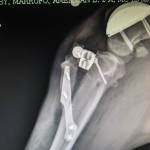

Beremiz Sánchez, encontró que Chavy presentaba luxación patelar grado IV -es decir que su rótula salió del surco de la rodilla-, y como consecuencia de ello sufrió desalineación del músculo cuadricep desarrollando a lo largo del tiempo una enfermedad degenerativa severa en su rodilla.

Además presentaba, ruptura del ligamento cruzado craneal, condición muy común en caso de luxación patelar y que predispuso a una mayor inestabilidad e inflamación articular.

El especialista detalló que el procedimiento a efectuarse era colocar un surco protésico para mejorar su condición biomecánica y contrarestar el dolor.

El procedimiento fue realizar el reemplazo del surco troclear PGR (patellar group replacement). “Se reemplazó el surco degenerado por una prótesis de titanio extra pulido o ultra pulido. Esta prótesis lo que busca es tener una superficie articular sumamente lisa para evitar que haya un roce inadecuado entre la rótula y la superficie articular degenerada”, indicó el especialista en ortopedia.